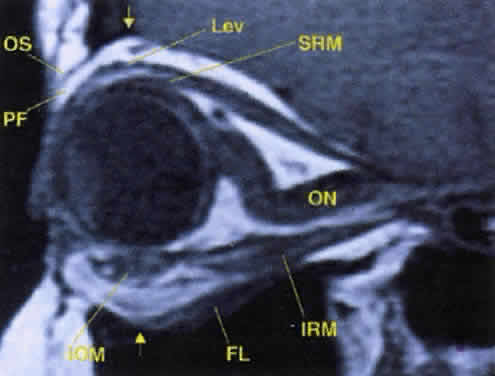

The orbit is surrounded on three sides by the paranasal sinuses (see Fig. 5). The ethmoid sinus runs along the medial orbital wall and is divided into anterior, middle, and posterior air cells by a highly variable system of septa. It is the only sinus to be fully pneumatized at birth. The thin lamina papyracea of the medial orbital wall and the vascular foramina for the anterior and posterior ethmoidal arteries provide scant resistance to the extension of infections and tumors from the ethmoidal sinus to the orbit, even in the adult (Fig. 10).

Fig. 10. The thin lamina papyracea provides little resistance to infection spread from the adjacent paranasal sinus. In this axial CT image of a 2-year-old child, opacification is noted within the ethmoid air cells. Note the subperiosteal collection along the medial orbital wall. In this case, the collection proved to be a sterile inflammatory phlegmon.